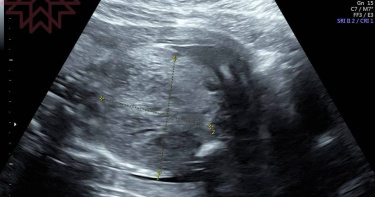

孕婦產檢發現「寶寶肚子有巨大腫瘤」 醫嘆:1周後胎兒心跳停止了

近日婦產科醫師蘇怡寧分享,一名孕婦之前產檢都很順利,但在20周例行產檢時,竟然發現胎兒的肚子裡有一顆巨大腫瘤,於是蘇怡寧馬上安排MRI核磁共振檢查,並轉診給另一位專業醫師尋求第2意見。不幸的是,過了一周孕婦再照超音波發現,胎兒的心跳已經停止了,讓蘇怡寧忍不住感嘆,「有時候我們不一定能改變上天的安排,結果不盡然都可以是美好的,但我們可以試著更平靜地走過這一段,休息一下,我們會再見面的」。蘇怡寧昨日在臉書發文,分享上個月有位媽咪原本產檢一切正常,但到了20周例行超音波檢查時,出現的畫面卻讓她感到有點震驚,原因是「寶寶的肚子有一顆巨大的腫瘤」。蘇怡寧透露,當時她看了好久,心中大概已有個想法,但最困難的其實是「該如何讓媽咪知道這件事情」。不過讓蘇怡寧意外的是,這位媽咪出乎意料的冷靜與勇敢,聽完後立刻問「接下來該怎麼辦」,於是蘇怡寧表示,會盡快幫忙安排MRI核磁共振檢查,並轉診給另一位專業醫師尋求第2意見,希望在最短的時間內釐清狀況。這位媽媽聽到真相後,表現的冷靜又勇敢。(圖/翻攝自蘇怡寧臉書)蘇怡寧說,一周後,這位媽咪回到她的門診,也已經知道寶寶的狀況不太樂觀,「我們也開始討論要如何準備接受這件事情,這時候超音波探頭一放上去,胎兒心跳停止了。不過,我們都做好準備了」。蘇怡寧感嘆,「有時候我們不一定能改變上天的安排,結果不盡然都可以是美好的,但我們可以試著更平靜地走過這一段,休息一下,我們會再見面的」。對此,許多網友心疼留言,「體貼媽媽的寶寶!會再回來的」、「懷胎10月,每一次的檢查總是抱持著一絲絲擔心,這樣的狀況都讓人心酸酸,但相信一切有最好的安排,寶貝會再用健康的身體來跟媽媽見面的」、「孩子有緣的話,會再回來的,其實本來就很少人,第一次懷孕能順產的」、「祝福媽媽跟寶寶有緣再相會」、「心疼,但相信會回來的」。